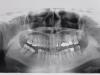

zubnikoff Опубликовано 19 августа, 2011 Поделиться Опубликовано 19 августа, 2011 Доброго времени суток.Жена попросила выложить снимок для оценки состояния зубов.Сама ужас как боится похода к стоматологу,хочет попросить Вас о предварительной консультации.Заранее огромное спасибо. Ссылка на комментарий

Alexandr dantist Опубликовано 20 августа, 2011 Поделиться Опубликовано 20 августа, 2011 верхние восьмые, нижний левый седьмой точно под щипцы. Ссылка на комментарий

Doc Опубликовано 21 августа, 2011 Поделиться Опубликовано 21 августа, 2011 Спасибо за ответ.А остальные впорядке? Нет, не в порядке, но по такому снимку точный диагноз не поставить. Ссылка на комментарий

Doc Опубликовано 25 августа, 2011 Поделиться Опубликовано 25 августа, 2011 А какой снимок нужен? Желательно прицельные на каждый проблемный зуб. Ну или хотя бы качественная цифровая ортопантомограмма, а не переснятая с пленки. Ссылка на комментарий